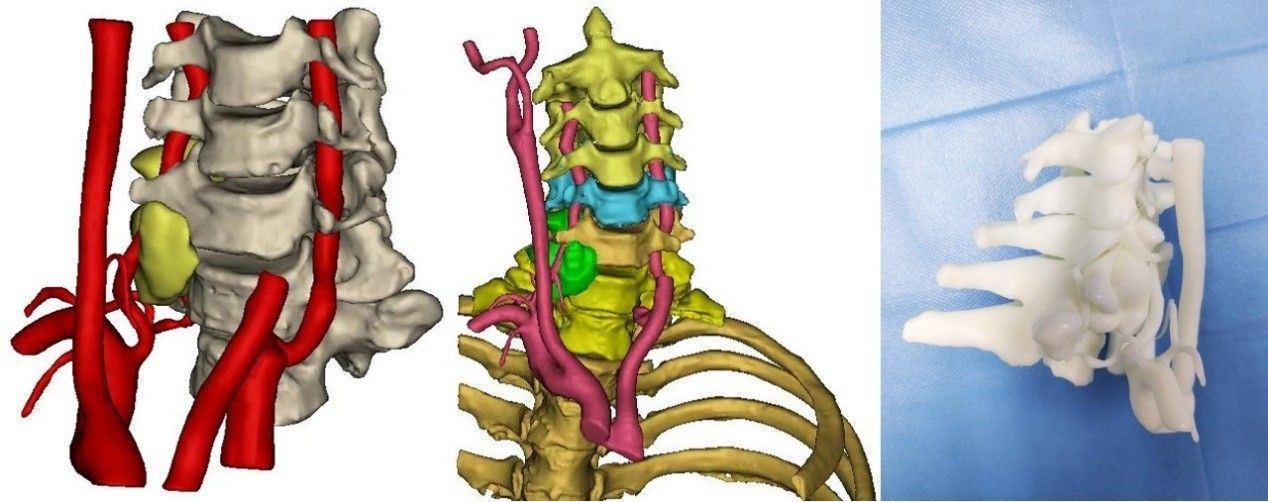

面对挑战,王栋主任亲自领衔,秦杰副主任医师、郭帅博士等手术团队术前联系耳鼻喉科、神经外科、影像科、输血科等协商,组织全科讨论,并制作3D打印模型模拟,凭借丰富的脊柱脊髓手术经验,制定了详细的、个性化的手术入路和计划及突发情况处理方案,最大程度减少手术创伤。术中,手术室董春力护士、麻醉科冯诚医生、肌电监护团队孙丽君技师等全程配合,王栋主任主刀,凭借对脊柱解剖的深刻理解,经颈前入路精准定位打开手术通道;在C6/7水平可见椎动脉迂曲,背侧与肿瘤粘连,肿瘤沿椎动脉向头端进入C6右侧横突孔,并与神经根关系密切,属于椎管内外沟通占位;遂采用显微外科技术逐层分离肿瘤和椎动脉、神经根及周围组织的粘连,从椎动脉内侧、外侧完整切除肿瘤,手术全程用时2小时左右,出血不到100ml,最大程度保护了患者神经功能。

术前规划